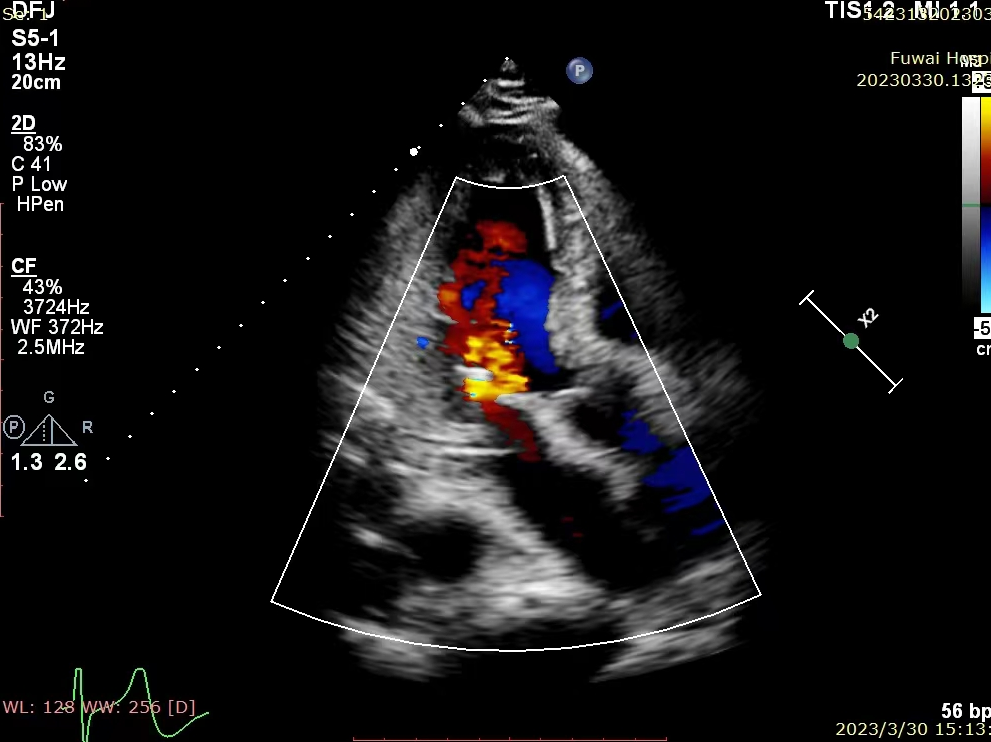

将MitraClip™推进至左心室,双臂朝向垂直于瓣叶边缘的长轴

将MitraClip™推进左心室并向后拉,直到二尖瓣瓣叶被抓捕,关闭夹子,反流几乎消失

手术过程